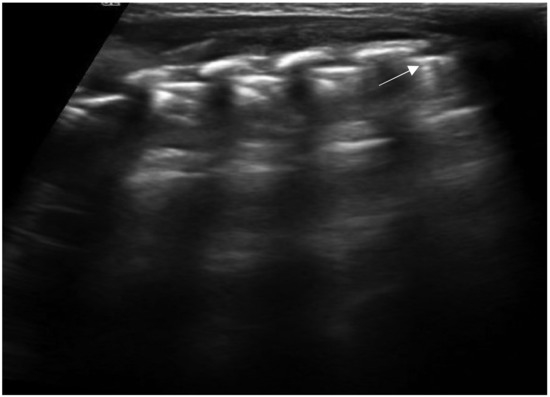

In bronchiolitis, the main ultrasound findings are: areas of subpleural consolidations defined as hypoechogenic areas with parenchymatous appearance and irregular margins, the presence of coalescent B-lines (three or more B-lines in each intercostal space) up to the “white lung” or focal presence of multiple B-lines (one or two B-lines in each intercostal space) and abnormalities of the pleural line (Figure 8 and Figure 9) [47]. Several studies demonstrated that lung ultrasound findings strictly correlate with the clinical evaluations in infants with bronchiolitis [48,49], and the 2020 consensus established LUS as a useful tool in assessing the severity of the disease [37]. Therefore, LUS could be used as support of the clinical examination in the identification of infants who may require more intensive care as supplementary oxygen or respiratory support [36].

Figure 8.

Bronchiolitis. Coalescent B-lines arising from the pleural line.